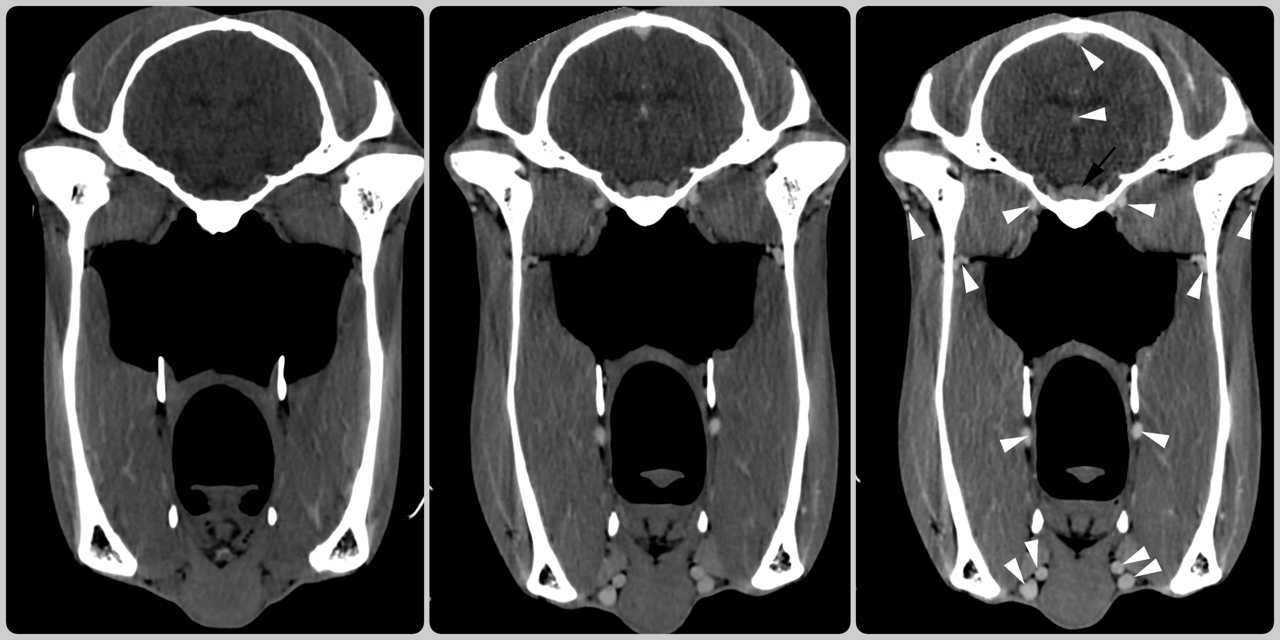

Same horse, same day ... so what have we done to make the CT scan on the left (image 1) look different from the middle one (image 2)?

We have injected contrast into the veins which we can see highlighting the blood vessels (white arrow heads) and the pituitary gland (black arrow) at the base of the brain (image 3).

(Image 1: pre-contrast; image 2: post contrast; image 3: marked up image showing contrast uptake)